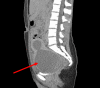

Vaginal agenesis is part of a group of anomalies, referred to as Mullerian anomalies due to their embryologic origin, in which there is a congenital absence of the vagina. We present a unique case in which a 20-year-old female presented to the Emergency Department with cyclical abdominal pain and primary amenorrhea. The original assessment showed a probable imperforate hymen; however, it was later found that she likely had vaginal agenesis. Vaginal agenesis is a rare disease, but it is prevalent enough that it should be kept at the forefront of the differential diagnosis in a woman with primary amenorrhea and recurring pain. We also highlight the importance of patient education in general, but categorically to sexual health.